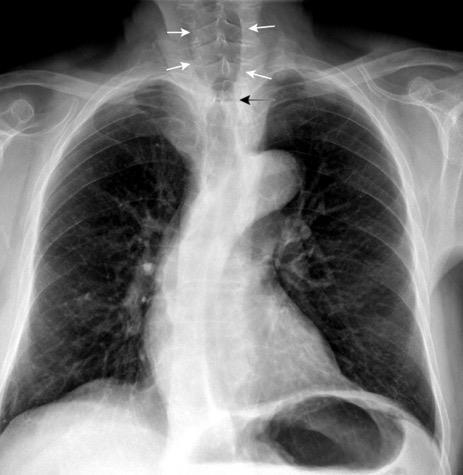

Pliegue axilar Normal

Rehúsa cirugía

2011. Acude por masa axilar

Linfoma NH de cél. B. Invasión Transtorácica.

Afectación axilar

Conglomerado adenopático axila derecha. Linfoma de Hodgkin.